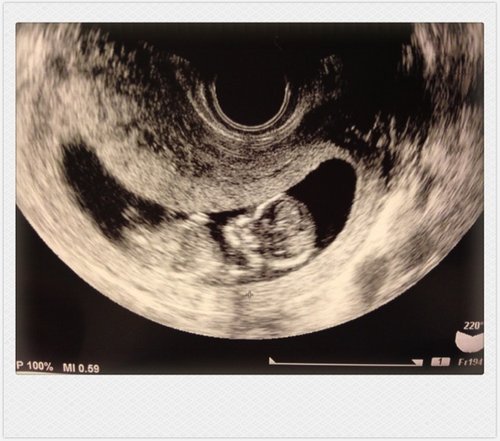

約莫一個星期之後(11W5D),我一步步邁向了上帝為我所預備的天堂の扉。

那一天我來到東京某婦產醫院做例行超音波產檢,心裡沒什麼期待,反正螢幕

裡應該仍舊是那一顆令人摸不著頭緒、有如陣露丸般的小黑球。但很明顯地,

我比我想像中地還要愚蠢,生命的變化豈是我這一介愚婦能參透!!子宮裡的

小生命竟然從一粒米大小的胚胎,逐漸變成一人形,能清楚看見頭、手、腳的

輪廓。儘管身長還不到五公分,但看著他翻滾著小小的身體,雙腳活潑地踢

動,霎時間我彷彿被世外高人打通了任督二脈,母愛混著眼淚一整個滿滿滿滿

溢了出來(←我真的在醫院裡給他丟臉地放聲大哭),突然覺得我這一生也實

在太值得、太偉大了,以前那些雞毛蒜皮的豐功偉業根本搬不上檯面,此刻的

我可是用自己的肉身在保護和孕育一個新生命耶~這世上還有什麼事情比這更

接近奇蹟呢?(←請見諒,孕婦的情緒起伏特別浮誇)。

那是我發現自己懷孕以來,第一次感受到懷孕的喜悅,覺得一切的辛苦都好值

得。還記得那天離開醫院時室外的氣溫才不過10度,但我的心卻暖烘烘地一整

天,情緒好激動,好想大聲宣告全世界:我要當阿母啦!꒰✩'ω`ૢ✩꒱